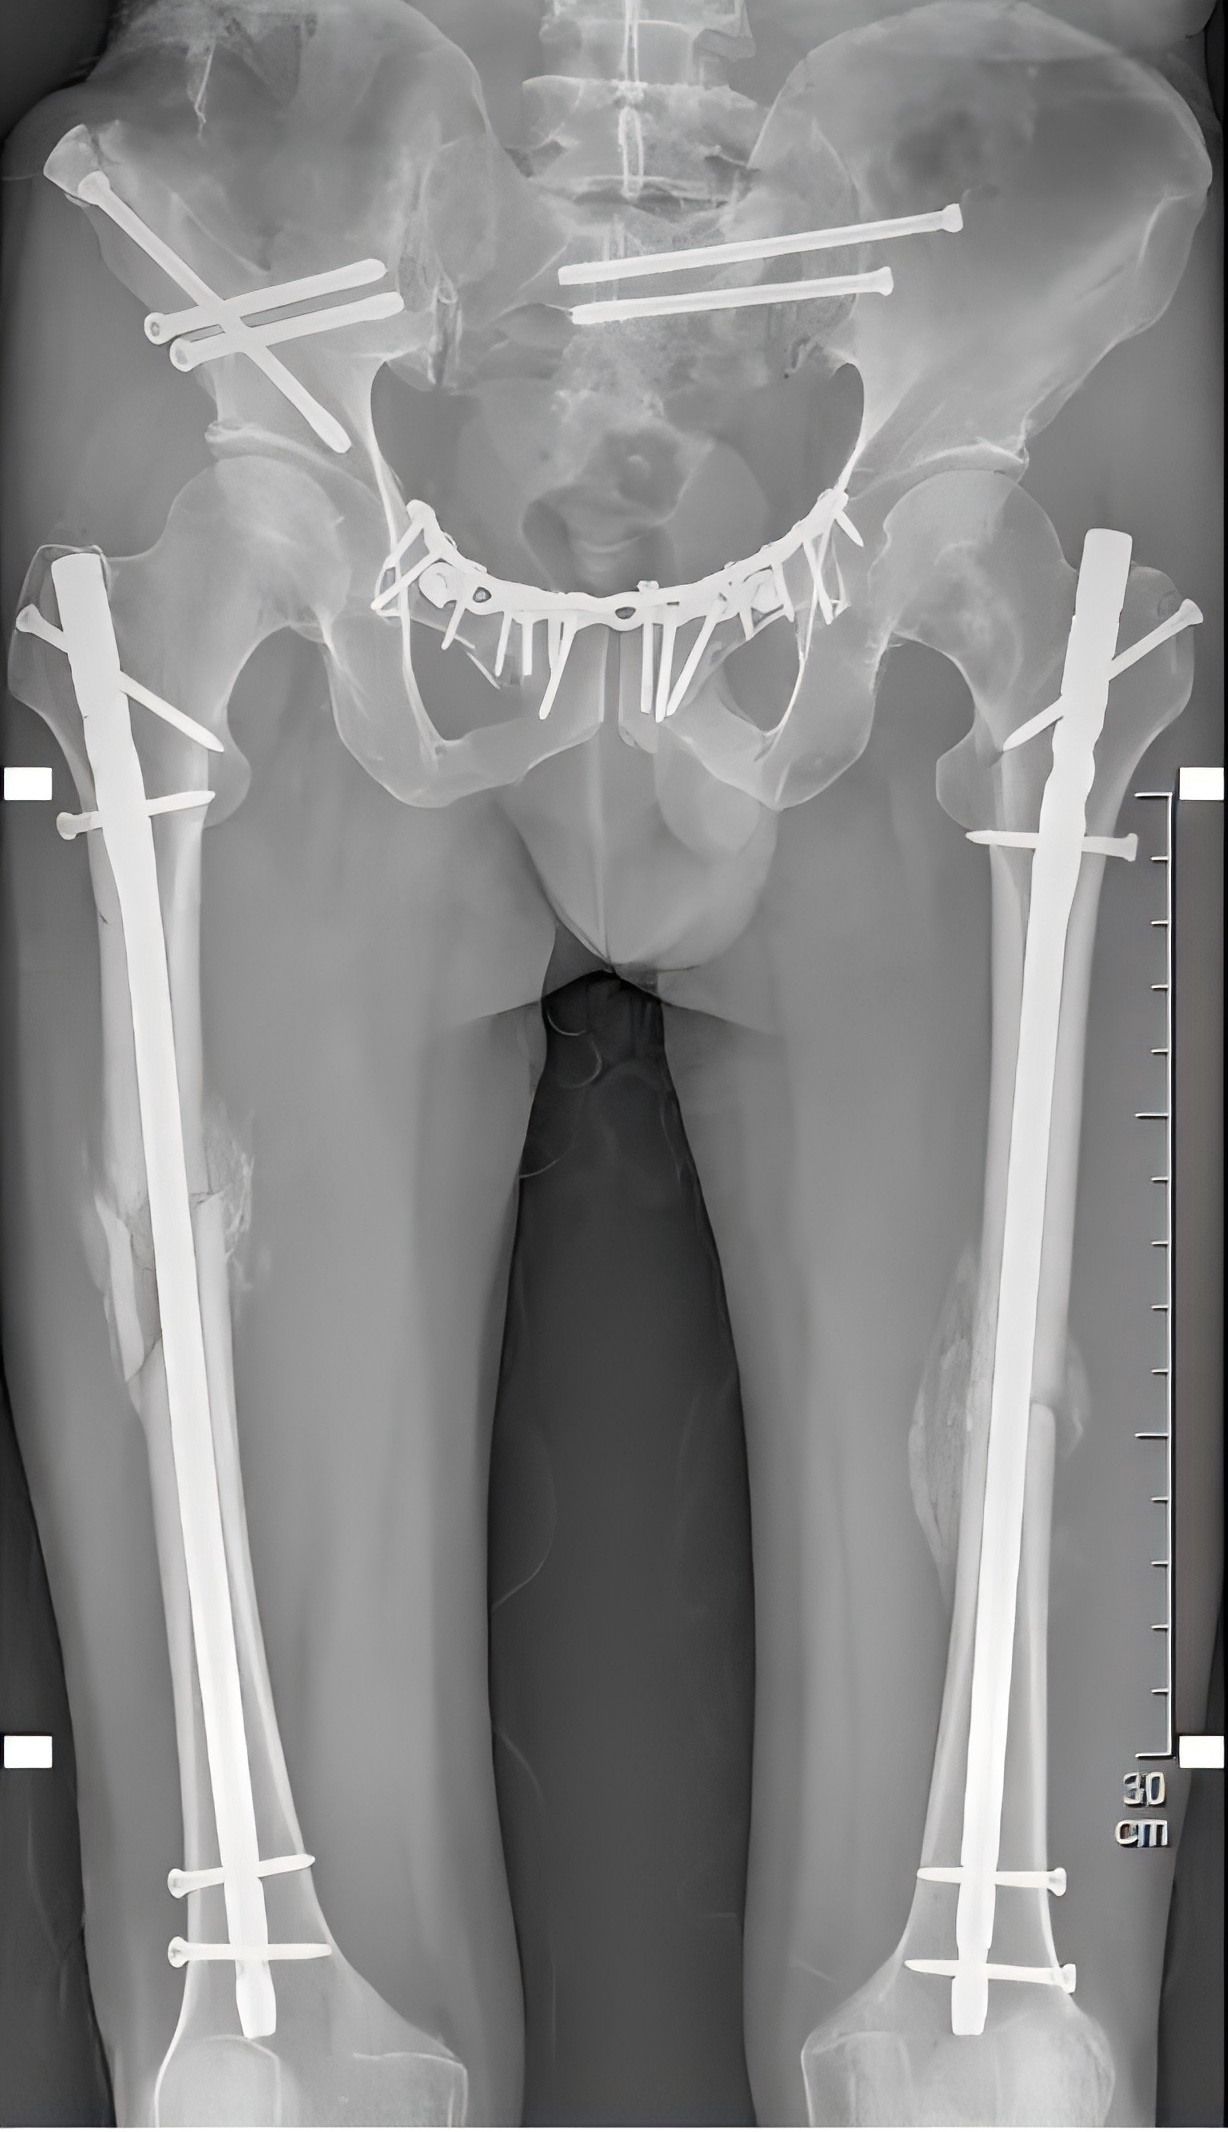

殷小軍團隊基于損傷控制理念,為患者量身定制了微創手術方案。手術分為兩期進行:待患者生命體征穩定后,一期先行骨盆及一側股骨骨折微創內固定治療;二期行另一側股骨骨折微創內固定手術。

醫療團隊僅用了11天,便為患者完成了多發骨折的手術治療。手術后一周,患者即可進行半臥、翻身活動,既減輕了護理難度,也增強了患者戰勝疾病的信心。

(患者術后X片)

術后1個月,復查顯示患者的骨折處愈合情況良好,大量骨痂形成。